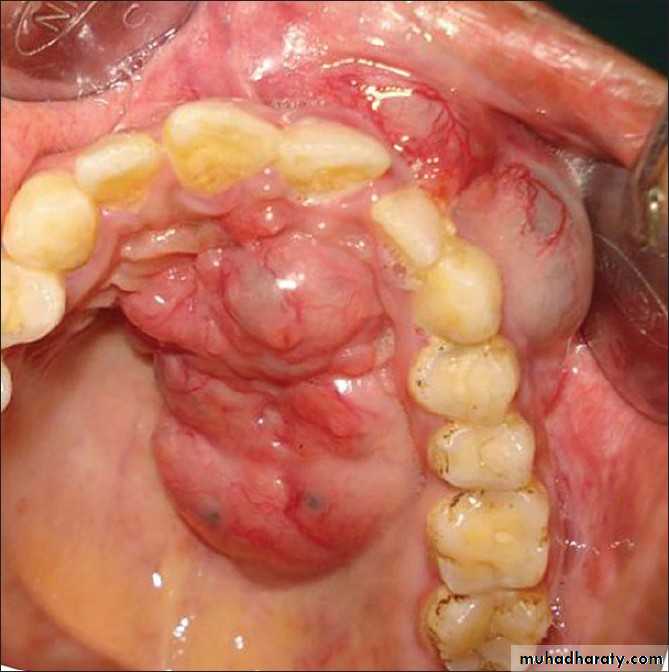

Pleomorphic Adenoma (Mixed Tumor)

Commonest tumour ( 53% - 71% ) of the salivary glandsTumor is slow growing, painless, solitary, firm, smooth, moveable without nerve involvement

Both mesenchymal / epithelial elements

Investigations include FNA, CT, MRIPleomorphic adenoma cont’d

Management

Superficial parotidectomy

total parotidectomy if deep lobe involvement

Recurrent rate 5% with superficial parotidectomy

Chance of turn to malignancy 3-10%